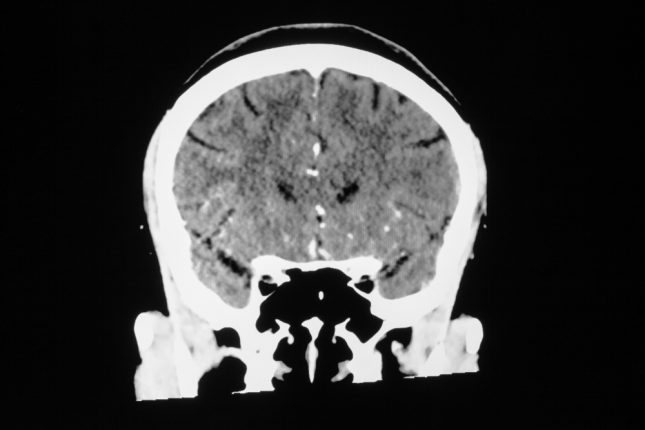

למרות שתרומבקטומיה אנדווסקולרית (EVT) בשבץ איסכמי חריף מומלצת על פי ההנחיות המקובלות לצורך שיפור ההתאוששות הפונקציונלית, עד כה אין מספיק נתונים על הקשר של פעולה זו עם שיעורי התמותה.

קבוצת חוקרים גרמנים פרסמו עבודה בכתב העת המוביל JAMA שנועדה לזהות מחקרים רלוונטיים המשווים את הטיפול ב-EVT לעומת טיפול רפואי אחר מבחינת שיעורי תמותה תוך 90 יום מהאירוע המוחי.